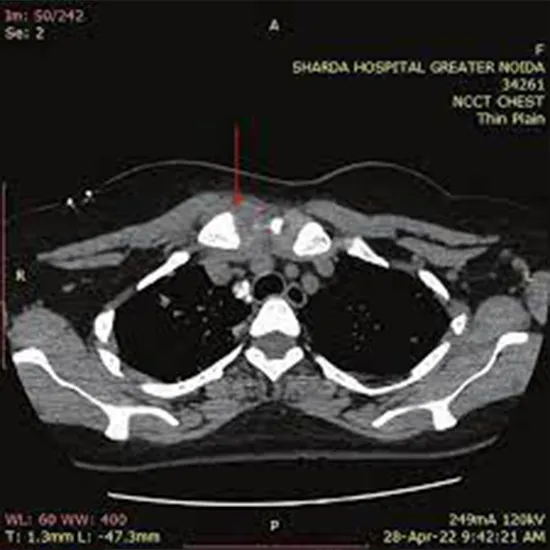

NCCT Sternoclavicular computed tomography (NCCT) is a non-contrast scan used to visualise the sternoclavicular joint and its pathology.

Doctors recommend this radiology scan to look for any underlying problems in the sternoclavicular joint concerns like:

• * Trauma

• * Dislocation of sternoclavicular

• * Lump

• * Deformity over SC joint

In this examination you need to lie supine on the scanning table and arms are placed on the sides then scans are performed. No contrast is used in this examination.